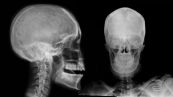

X quang sọ là một loạt các hình ảnh về xương của hộp sọ, trong trường hợp khẩn cấp, bác sĩ có thể thấy kết quả ban đầu của X quang sọ trong vài phút. Để hiểu rõ hơn về phương pháp này cũng như ý nghĩa lâm sàng giá trị kết quả của nó, mời các bạn tham khảo bài viết dưới đây nhé!